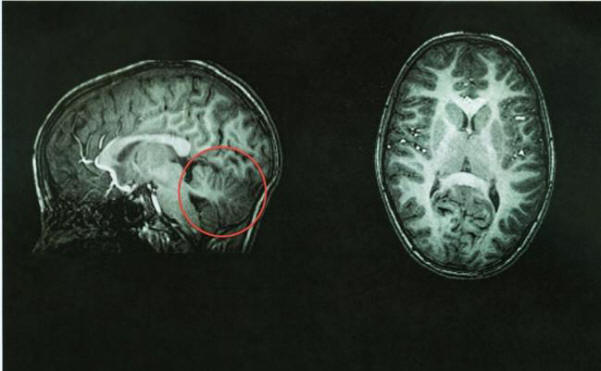

Po tomografii lékaři okamžitě identifikovali zdroj problému – jeho mozeček chyběl. Prostor, kde by měl být prázdný. Tohle oblast mozku byla naplněna mozkomíšním mokem, poskytuje ochrana proti nemoci. Mozeček zabírá asi 10 procent celkový objem mozku, ale obsahuje 50 procent neuronů.

Zobrazování mozku čínské ženy bez mozečku

Foto z otevřených zdrojů